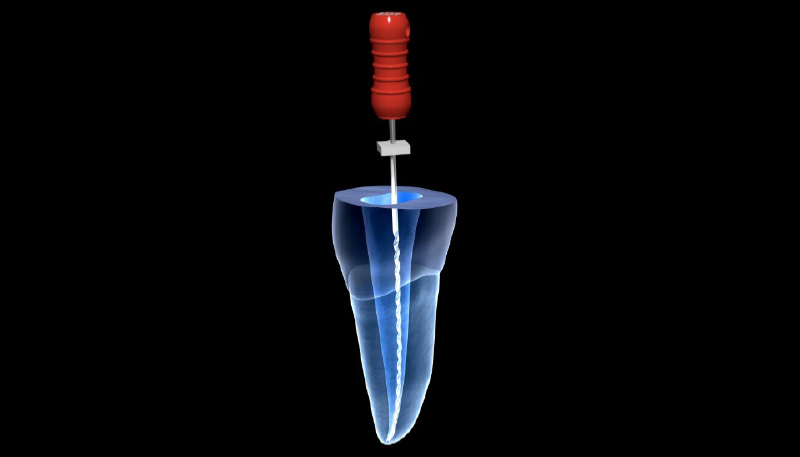

根管治療の具体的な治療内容

歯の根っこ(神経)の中から痛みや腫れの原因である「感染した汚染物」を、取り除く治療です。

針のような道具を使って、感染した汚染物をとりのぞいていきます。

汚れを取り除いた箇所をキレイに清掃・消毒して、お薬で埋めるまでが根管治療です。